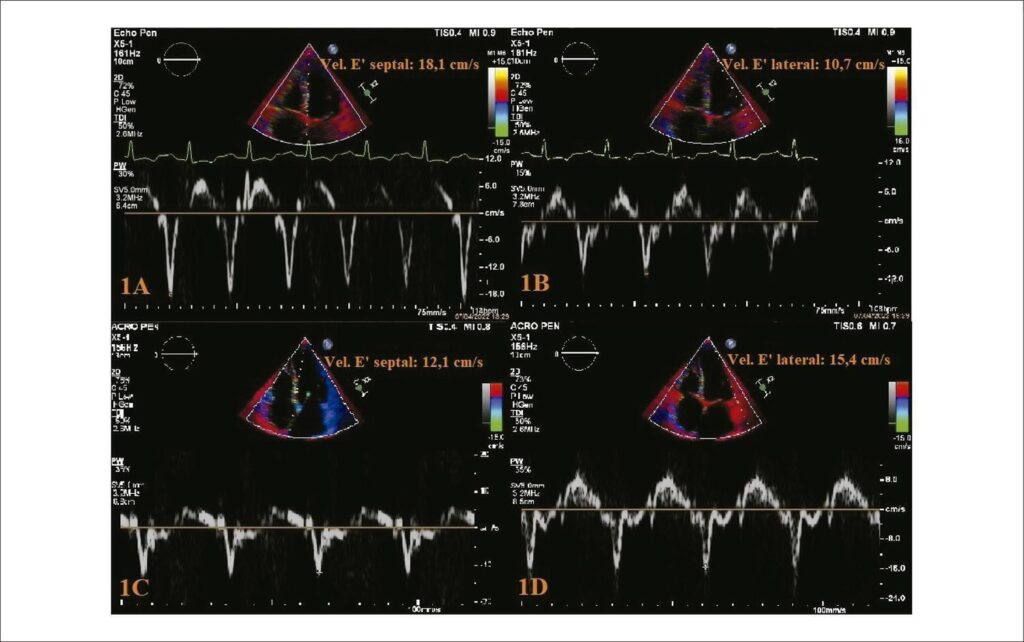

A pericardite constritiva (PC) é uma condição na qual a cicatrização e perda de elasticidade do pericárdio resultam em enchimento ventricular prejudicado, disfunção diastólica e insuficiência cardíaca direita. O diagnóstico dessa patologia é desafiador, sendo frequente a necessidade de técnicas de imagem multimodal, dentre as quais a ecocardiografia representa a modalidade de imagem inicial para a avaliação diagnóstica, além de permitir a diferenciação da PC da cardiomiopatia restritiva (CMR) e outras condições que mimetizam constrição.